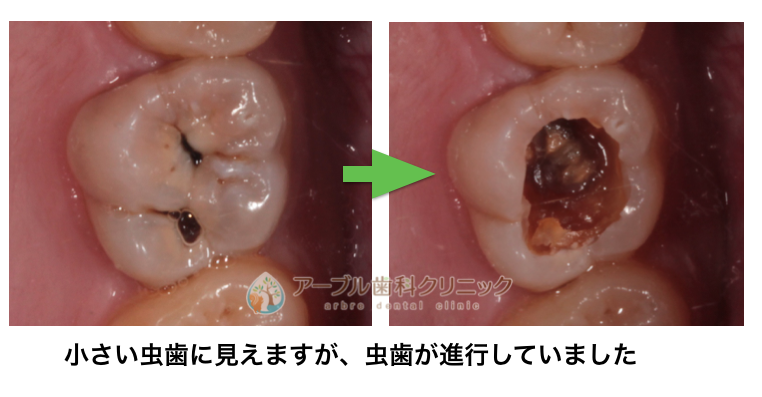

今まで虫歯と言われなかった歯に虫歯が見つかった症例

歯の間に虫歯がありました

さらに治療してみると虫歯が内部でかなり進行していました

歯の内部の虫歯(茶色いところ)を取り除くと

ここまで虫歯菌で歯が溶けていました

ここまで虫歯になっていても自覚症状はありません